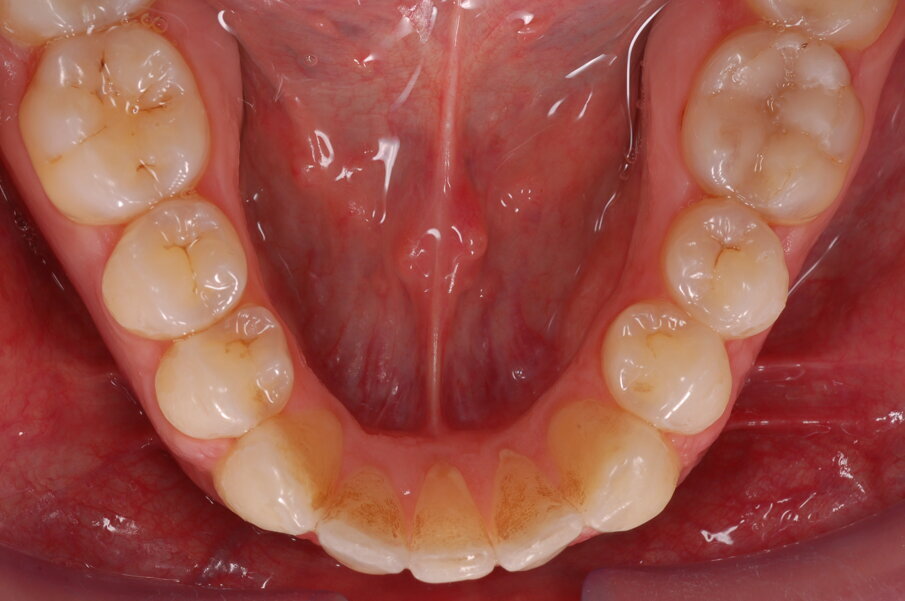

Diagnosi ed eziologia Un uomo sano di 39 anni si è presentato nel nostro studio ortodontico lamentando un aspetto dentale poco attraente e la paura della chirurgia ortognatica proposta da un altro ortodontista. Clinicamente, il profilo del paziente era rettilineo e la vista frontale non mostrava alcuna asimmetria facciale. L’esame funzionale non ha rivelato alcuna deviazione mandibolare o riduzione dei movimenti. Il paziente non aveva dolori articolari e non sono stati rilevati rumori articolari. Era presente una lieve occlusione molare bilaterale di Classe II, un morso aperto e un grave affollamento in entrambe le arcate. L’affollamento era particolarmente grave nell’arcata mandibolare, sebbene mancasse l’incisivo centrale mandibolare destro. Gli incisivi mascellari erano di piccole dimensioni, suggerendo una discrepanza dell’indice di Bolton se fossero stati presenti tutti e quattro gli incisivi mandibolari. Erano inoltre presenti un morso incrociato nella regione dell’incisivo laterale superiore sinistro e una grave rotazione distale del secondo premolare mandibolare sinistro (Figg. 1-8).

Figg. 1-8_Fotografie facciali e intraorali pre-trattamento.

Figg. 25-29_Progressi clinici dopo 12 mesi di trattamento con allineatori.